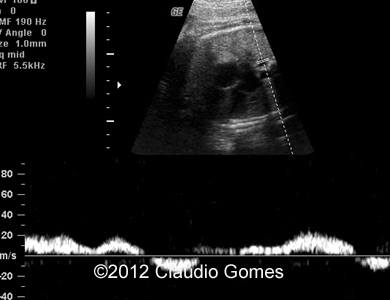

Images 8-11: Persistent right umbilical vein and Inferior vena cava interruption with continuity of the flow via Azygos vein on grayscale and color Doppler

Fig8

Fig9

Fig10

Fig11